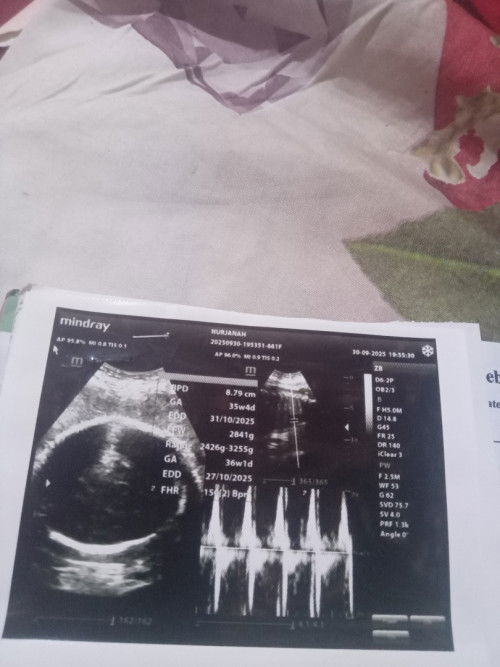

Mendamba seorang anak

Kalo aku sering pegel pinggang Kalo apis nyuci kaya abis kecapean kenapa ya bun